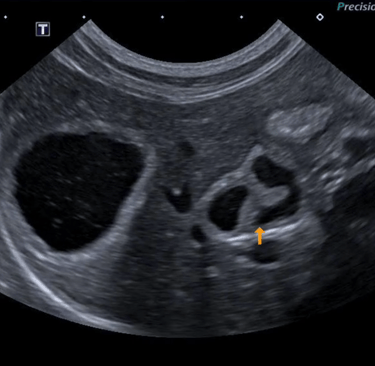

8 - Quels organes sont visualisables ici ?

A - La Vessie

B - Le Foie

C - La Vésicule biliaire

D - La prostate

E - La Rate

F - Le canal cystique

G - Le canal cholédoque

9 - Sur cette même image échographique que pouvez-vous dire ?

A - J'observe la présence d'un calcul biliaire

B - Je n'observe aucune anomalie

C - J'observe la présence d'une mucocoele biliaire

D - J'observe la présence d'une cholangite

E - J'observe la présence d'une cholécystite

Question 8 : Réponses B,C,F,G

Question 9 : Réponses D, E